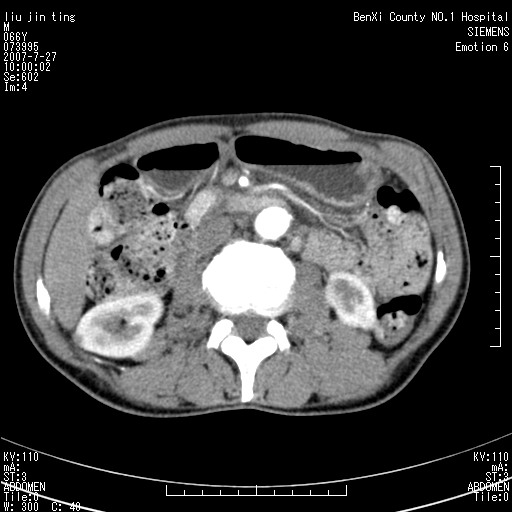

腹痛,背痛,无恶心呕吐,不黄,彩超示胰腺钩癌,ct扫描病灶平扫30-40hu,增强后动脉期40--60hu,静脉期50-68hu,真的是钩突上的么?您要试一试么?

动脉期

静脉期